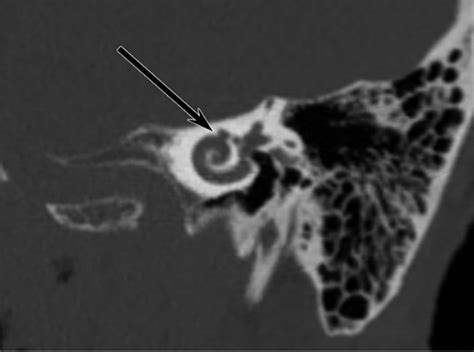

Diagnosing Semicircular Canal Dehiscence requires a combination of clinical history and specialized imaging. Because the opening in the bone is often microscopic, standard imaging may not be sufficient. Physicians typically rely on specific protocols to confirm the presence of the dehiscence.

High-Resolution CT (HRCT) Visualizing the temporal bone to identify the specific site of the dehiscence.